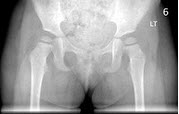

25、单项选择题

女,26岁,骶髂部疼痛2年余,间歇发作,结合图像,最可能诊断是()

A.致密性髂骨炎

B.化脓性髂骨炎

C.结核性髂骨炎

D.强直性脊柱炎

E.骶髂关节退行性变